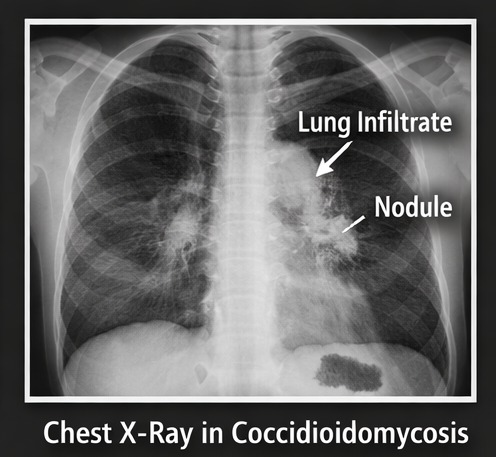

Chest Imaging

Chest X-ray demonstrated:

• Right lower lobe consolidation

• Ill-defined nodular opacities

Coccidioidomycosis is an often underrecognized fungal infection that can mimic common respiratory conditions such as pneumonia or tuberculosis, leading to potential delays in diagnosis. A detailed exposure history, including travel to endemic areas or dust exposure, is essential in raising clinical suspicion. Diagnosis relies on a combination of serological testing for Coccidioides-specific antibodies and imaging findings, which may show pulmonary infiltrates, nodules, or lymphadenopathy.